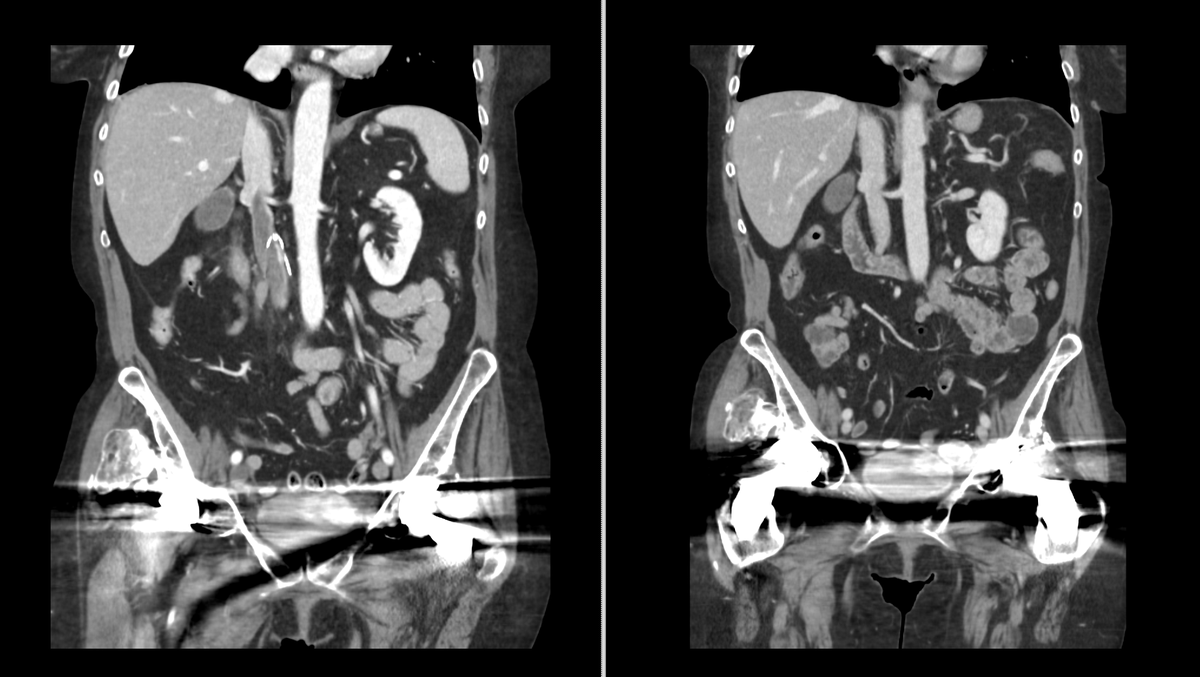

Young patient (30’s) w/ small PE & #symptomatic #subacute #iliocaval #DVT extending above #IVCFilter. #Inari #ClotTriever #Thrombectomy

0

6

40